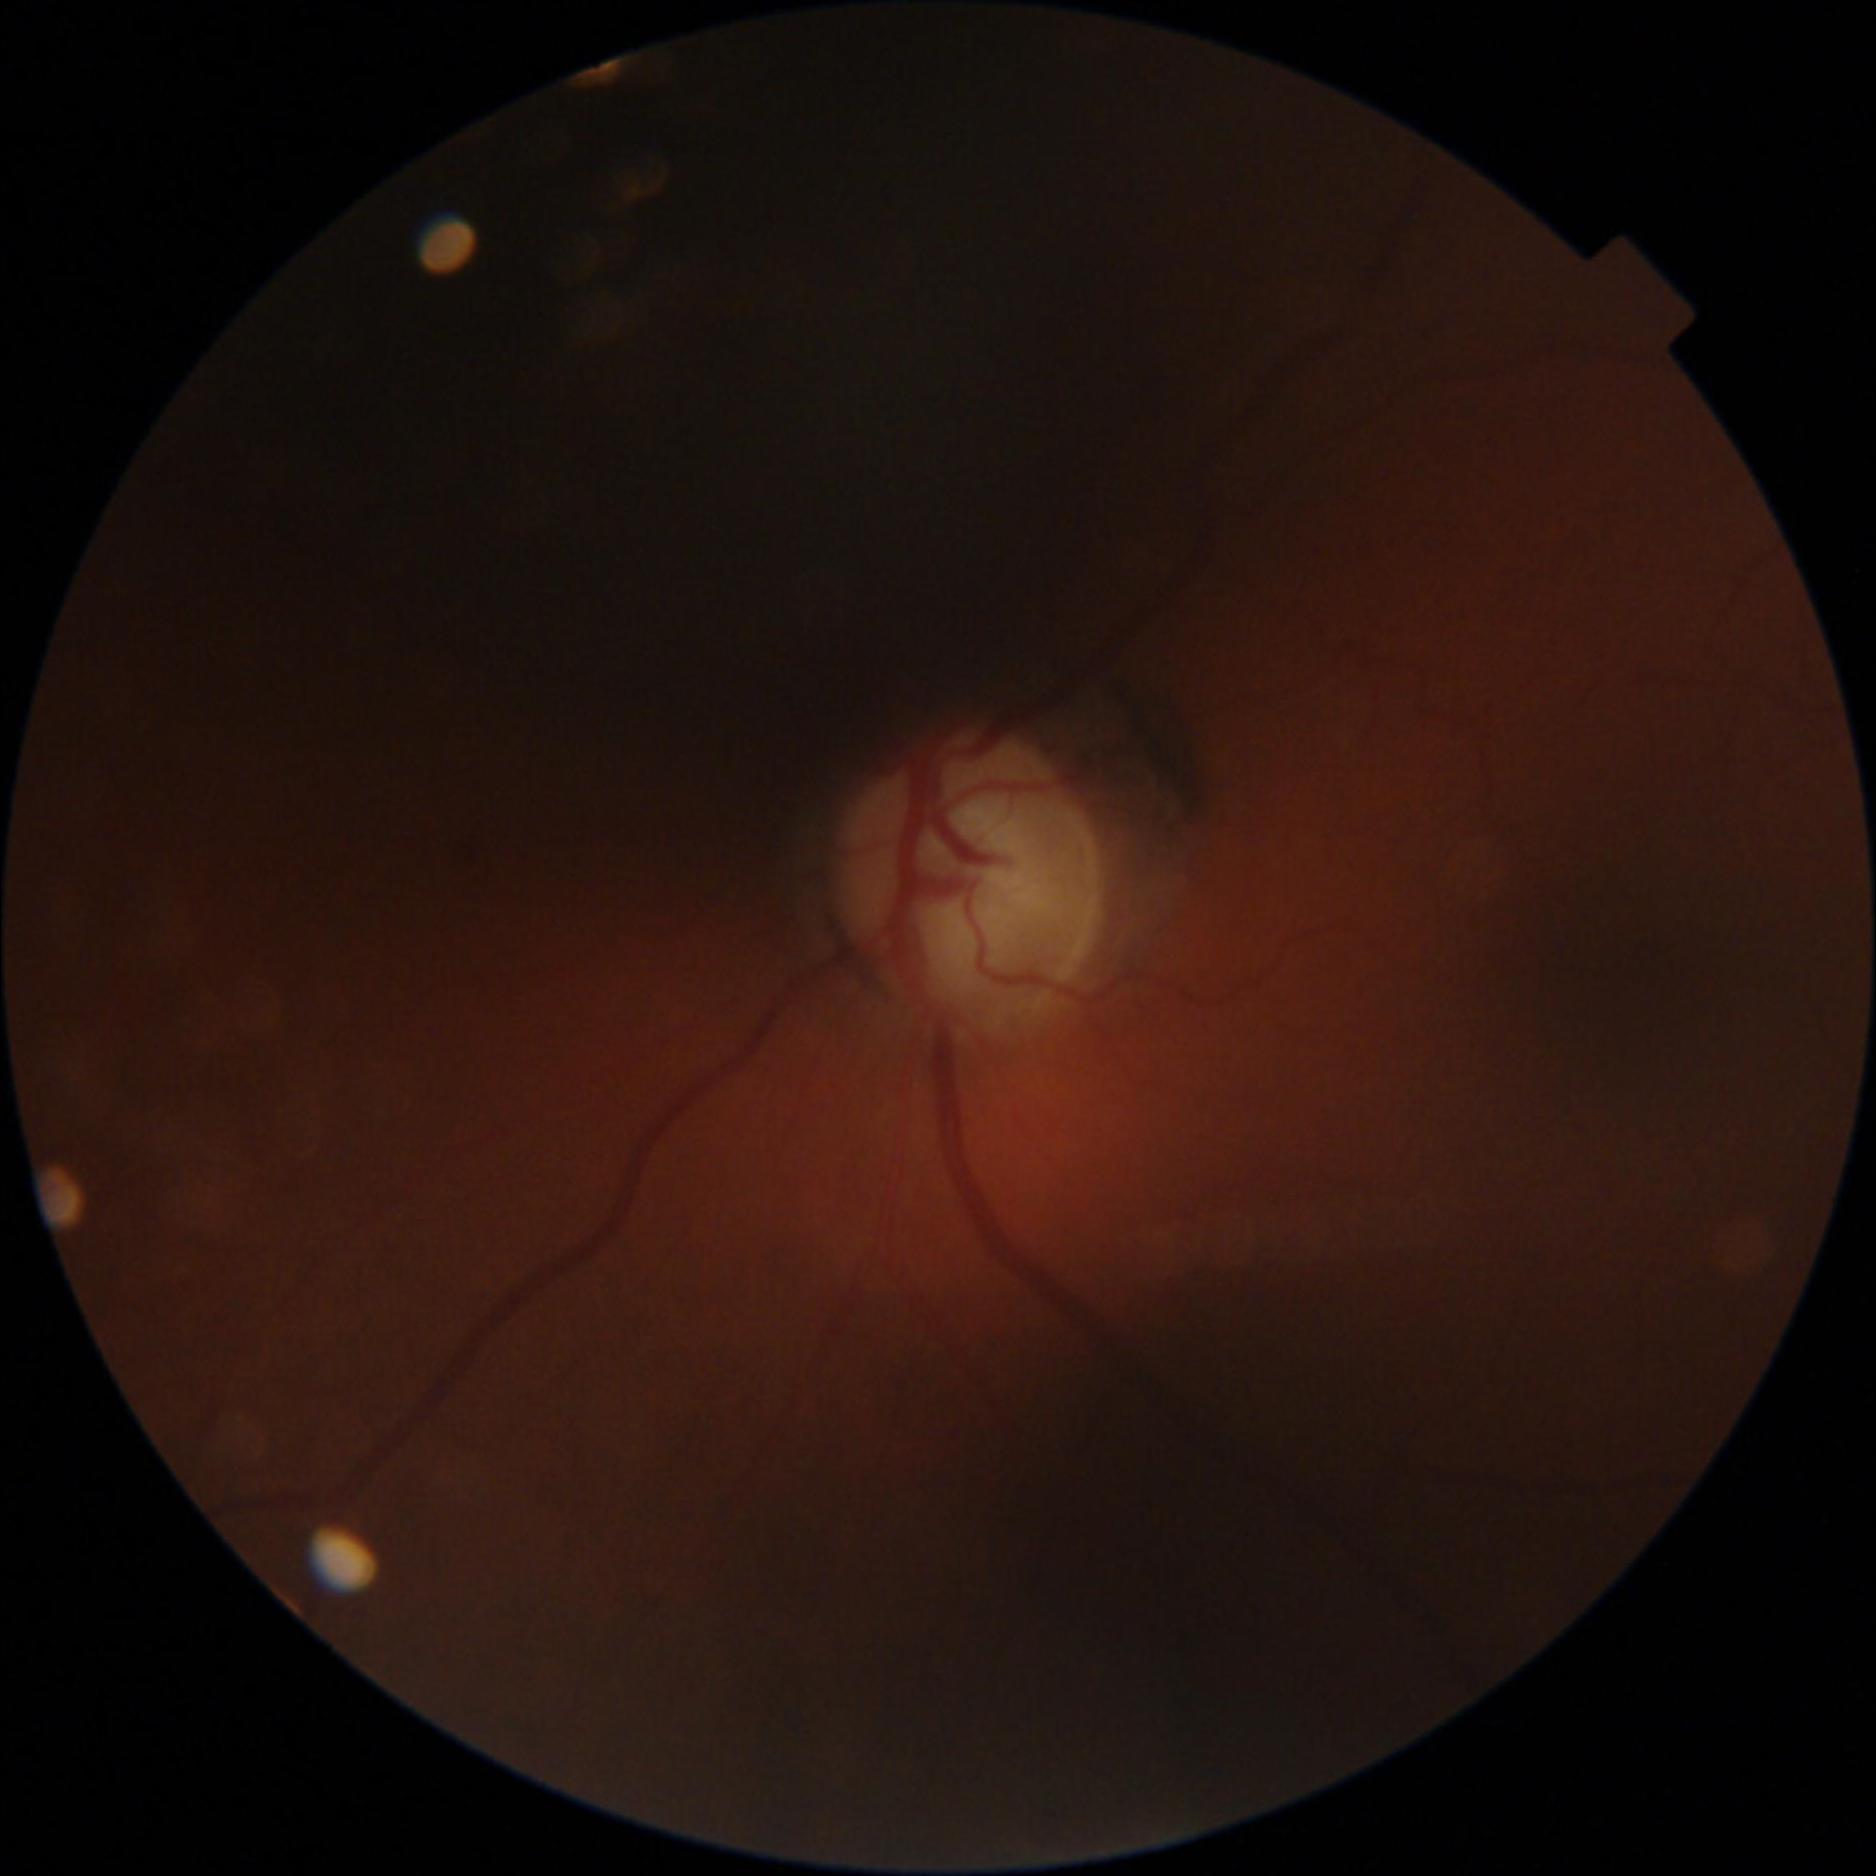

GON is diagnosed through a comprehensive ophthalmic examination that includes intra-ocular pressure (IOP) measurement, anterior chamber and angle assessment, optic disc (OD) inspection, visual field assessment, and optic nerve head imaging [1, 4]. Although effective, these procedures require the expertise of an ophthalmologist and access to specialized, often costly, equipment, which can be a limiting factor. Alternatively, computer-aided analysis of digital fundus images (DFI) can be used to identify GON. DFIs are captured using a fundus camera, which photographs the posterior segment of the eye and provides a clear view of the OD [5].

Recent studies have increasingly utilized deep learning (DL) models for automated GON detection using DFIs [6–8]. However, a major limitation in published research is that GON reference labels are often derived solely from DFI evaluations rather than comprehensive ophthalmic examinations [9–12]. This approach intrinsically reduces the GON detection task to a subjective evaluation of the OD, which has inherent limitations in identifying GON. Consequently, DL models trained exclusively on DFIs may inherit biases, be influenced by subjective interpretations, and inconsistent annotations, include examples that are not verified and potentially diverge from the true clinical manifestation of GON. Additionally, this method can be error prone, since other ophthalmic conditions may mimic the appearance of a GON cupped optic disc, such as ischemic optic neuropathy and compressive optic neuropathy [13].

The dataset was curated by the Hillel Yaffe Ophthalmology Department Glaucoma Unit, Hadera, Israel, between 2022-2024. DFIs were captured using a TOPCON DRI OCT Triton retinal camera with a 45° FOV. The dataset includes subjects aged 36 to 95 years, with 73% of the DFIs classified as glaucomatous. Patient selection followed specific inclusion and exclusion criteria to ensure data quality and clinical relevance.

All DFIs were deidentified, ensuring that any personal identifiers were removed. To maintain consistency, images were cropped to a square format by removing black borders. A quality score for each DFI was computed using FundusQ-Net [5] and is included in the dataset.

The dataset consists of 747 DFIs, including:

- 548 glaucomatous DFIs (73%)

- 199 non-glaucomatous DFIs (27%)

- Quality score range: 1-10 (scored using FundusQ-Net [5])

- Mean quality score: 5.9 ± 1.0